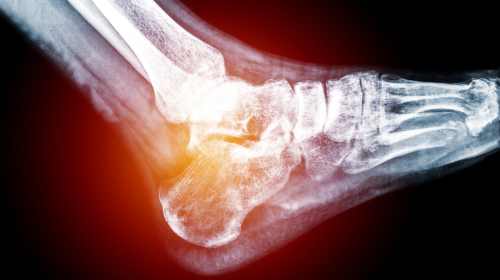

- Traumatic and sports injuries

- Fractures of the lower extremity